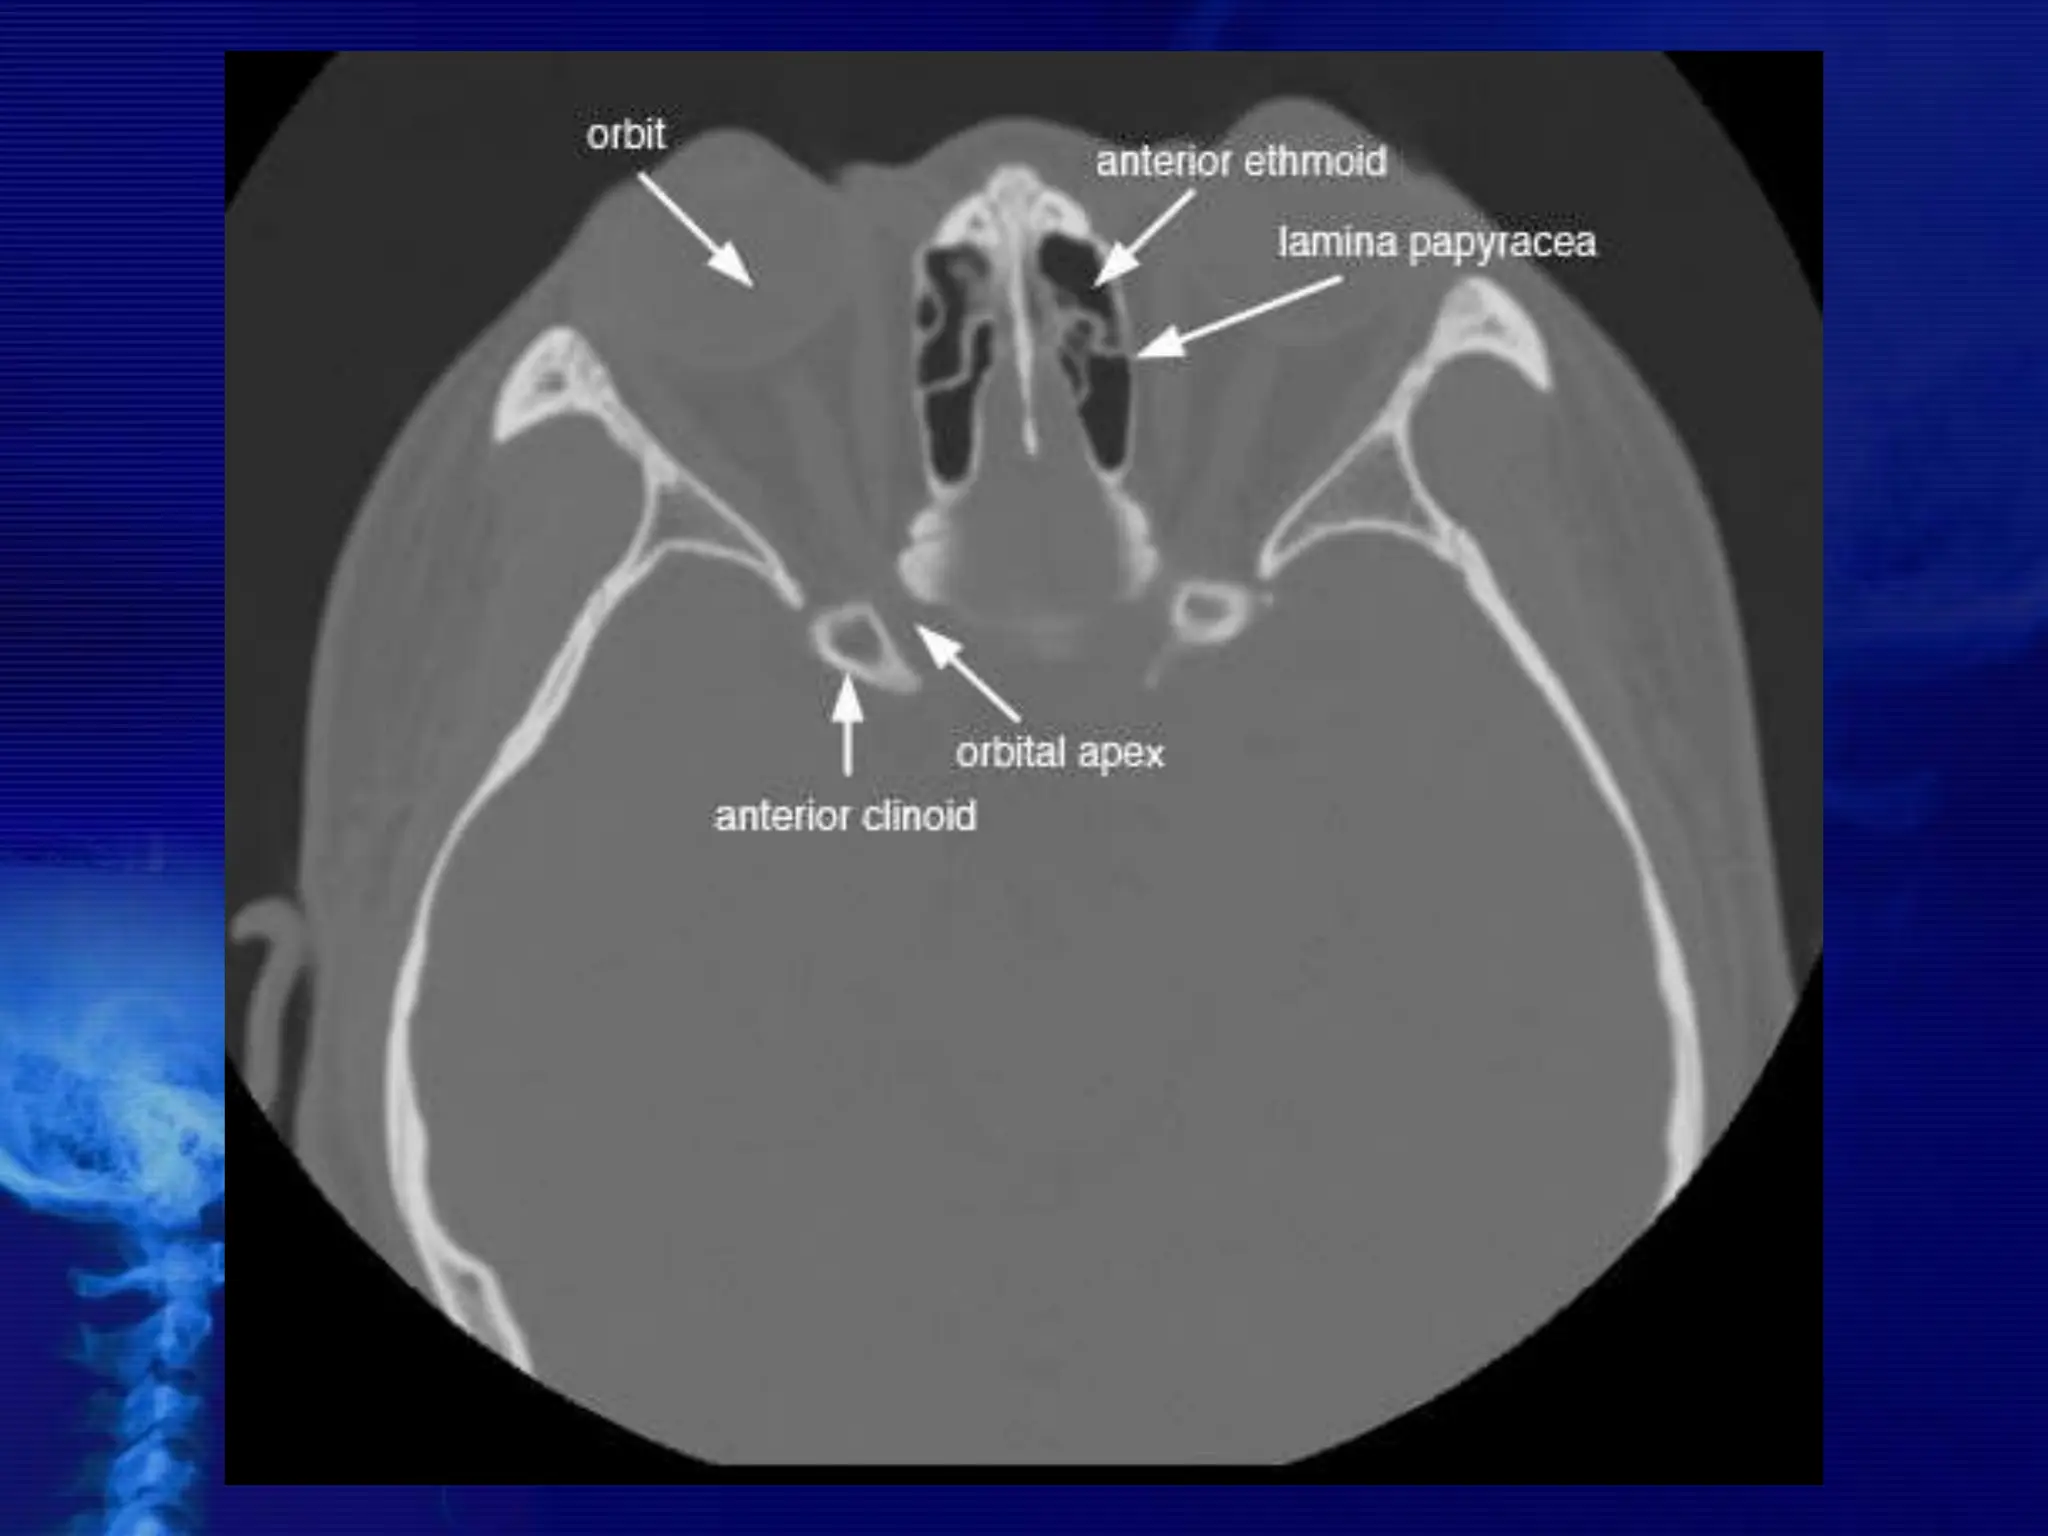

Ethmoid Sinuses

The ethmoid sinuses are contained within the lateral masses or

labyrinths of the ethmoid bone. These air cells are grouped into anterior,

middle, and posterior collections, but they all intercommunicate.

When viewed from the side, the anterior ethmoid sinuses appear to fill

the orbits. This occurs because portions of the ethmoid sinuses are

contained in the lateral masses of the ethmoid bone, which helps to form

the medial wall of each orbit.

CT NOSE

AND PNS

BASIC CONCEPTS

• CT scans typically obtained for visualizing the

paranasal sinus should include coronal and axial (3-

mm) cross

sections.

 Soft tissue and bony windows facilitate evaluation of

disease processes and the bony architecture.

 The use of intravenous contrast material just prior

to scanning can help define soft tissue lesions and

delineate vascularized structures, such as vascular

tumors.

 Contrast-enhanced CT is particularly useful in

evaluating neoplastic, chronic, and inflammatory

processes.

 The CT scan is the GOLD STANDARD

investigation in all preoperative cases as it

gives detailed bony anatomy of the area

and serves as a ‘road map’ for the

operating surgeon.

 CT scans are best done after a course of

antibiotics, so that acute inflammation is not

mistaken for chronic mucosal disease.

CROSS SECTIONAL ANATOMY –

AXIALS